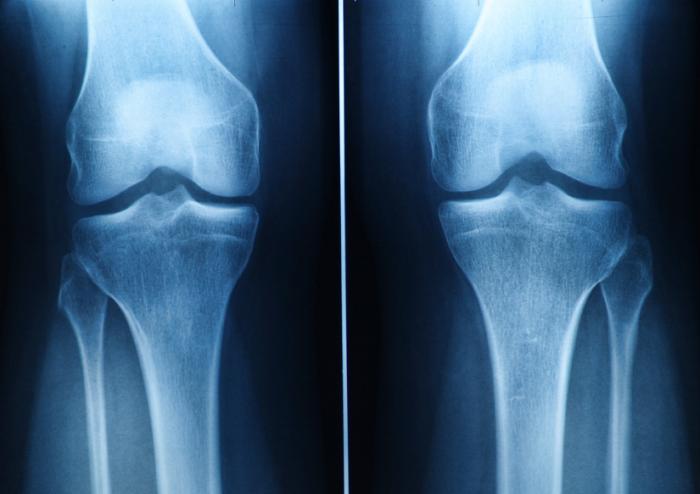

Cartilage Problems

Here, we are developing novel therapeutic approaches for the regeneration of Articular Cartilage. Our goal is to provide long-term solutions to cartilage problems affecting large segments of populations through regenerative medicines. Our cartilage regenerative tools are based on biomaterial scaffolds and cell therapy and could be translated into clinical treatments. These approaches are novel and provide a promise of profoundly improving the quality of life for patients.